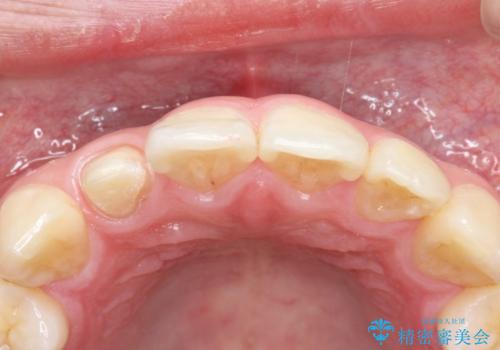

- 前歯が痛いことを主訴に来院されました。

顕微鏡やラバーダムを使用した根管治療を行ってくれる病院を探していたそうです。

当院の根管治療は100%ラバーダムを使い無菌的な処置に配慮して行っております。

今回は歯冠修復にe-maxプレスクラウンを使っています。